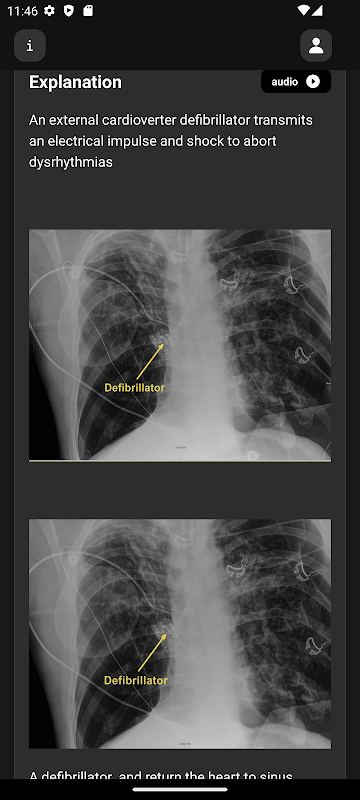

علم الأشعة الأساسي لطلاب الطب هو تطبيق تعليمي مصمم لتعزيز معرفتك بالأشعة من خلال أسئلة متعددة الاختيارات (MCQs) منسقة بعناية مع صور ومقاطع فيديو ورسوم متحركة عالية الجودة.

صور إشعاعية ومقاطع فيديو ورسوم متحركة عالية الجودة

شرح تفصيلي لكل سؤال